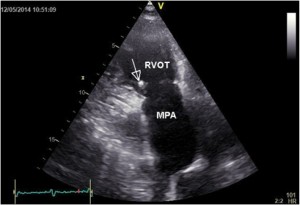

A 33-year-old man who had been diagnosed with PDA in childhood was refferedfor cardiac evaluation for fatigue and progressively worsening dyspnoea on exertion over the past 3 months. Physical examination revealed an afebrile patient, hyperdynamic precordium, a continuous murmur with thrill over the pulmonary area, peripheral oedema and hepatomegaly. The blood pressure was 120/60 mm Hg and the peripheral pulses were prominent. Auscultation of the lungs revealed mild basal crackles bilaterally. There were no clinical stigmata consistent with endocarditis. The ECG showed sinus rhythm at 78 bpm, biatrial abnormality, signs of left ventricular hypertrophy and complete right bundle branch block. There was no inflammatory syndrome or anemia. Transthoracic and transesophageal echocardiography confirmed the presence of a large PDA (defect size 11 mm), with a continuous systolic-diastolic flow signal with high velocities (up to 4.8 m/s) recorded by continuous wave Doppler examination at the level of this turbulent jet from the descending aorta to the pulmonary artery (Figures 1-3). The left ventricle was severely dilated (EDV/ESV=247/124 ml), with mild global systolic dysfunction (ejection fraction of 50%). The assessment of pulmonary artery systolic pressure was carried out by measuring peak tricuspid regurgitation velocity and the estimated value was 52 mm Hg. The TTE exam also revealed mobile vegetations on the pulmonary valve, with severe valve destructions, lack of coaptation and severe, free pulmonary regurgitation on color Doppler examination (Figures 4, 5). No vegetations were seen on the other valves, cardiac chambers or great vessels.

Figure 4. Transthoracic parasternal short axis views vegetations (arrow) on a pulmonary valve with destructions and lack of diastolic coaptation. RVOT- right ventricular outflow tract, MPA- main pulmonary artery.